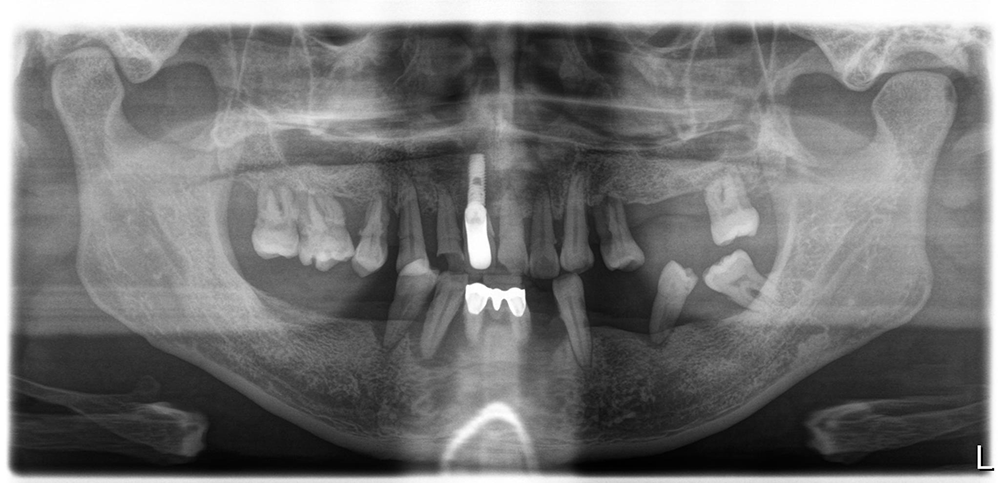

영상에서 보시는 것처럼 치료전 치아상태가 아주 좋지 않습니다. 치조골이 모두 녹아서 치아들이 많이 흔들릴뿐 아니라 치석과 프라그가 치아에 잔뜩 붙어있습니다. 이런 상태를 보았을 때 우리는 전체임플란트 치료후 위생관리를 더 신경쓰게 해야 한다는 것을 생각하게 됩니다.

이 환자분은 40대의 젊은 남성이었는데 아무래도 치아가 하나둘 망가지면서 관리를 포기한 상태였던 거 같습니다. 입 안에 임플란트가 앞니에 하나 있었는데 해당 임플란트는보기에 흉하게 만들어져 있을 뿐 아니라 이미 임플란트주위염이 생겨져 있어서 해당 임플란트도 다른 치아처럼 제거를 하기로 했습니다.